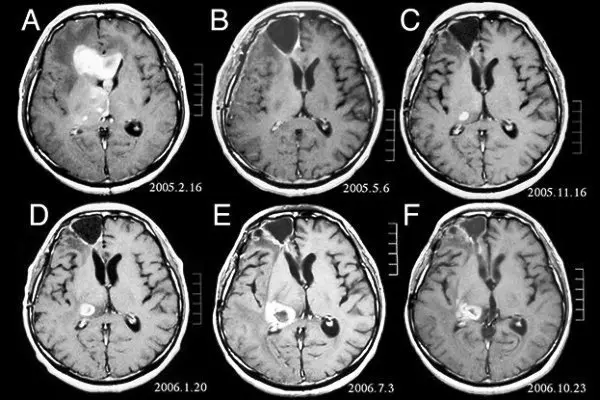

مطالعه جدید نشان می دهد سی تی اسکن که عمدتا در تصویربرداری های پزشکی استفاده می شود ریسک تومورهای مغزی را افزایش می دهد.

استفاده از سی تی اسکن در طول دو دهه اخیر به شدت افزایش یافته است. درحالیکه این شیوه بسیار موجب افزایش توانایی های تشخیصی شده است، اما در آن، از دوز بالاتر اشعه نسبت به شیوه های تشخیصی دیگر استفاده می شود. ازاینرو این میزان اشعه مورداستفاده، بخصوص در کودکان، نگران کننده است چراکه بدخیمی های مرتبط با این اشعه ها در کودکان بیش از بزرگسالان است.

لوسمی (سرطان خون) و تومورهای مغزی از شایع ترین بدخیمی های ناشی از رادیواکتیویته در بین کودکان و افراد جوان هستند. از اینرو محققان به ارزیابی ریسک تومور مغزی و لوسمی در کودکان بعد از قرارگیری در معرض اشعه ناشی از سی تی اسکن پرداختند.

محققان در این مطالعه، یک گروه از کودکان هلندی به تعداد ۱۶۸,۳۹۴ نفر را که بین سال های ۱۹۷۹ تا ۲۰۱۲ تحت سی تی اسکن قرار گرفته بودند مورد بررسی قرار دادند و به ارتباط آن با سرطان پی بردند.

نتایج نشان داد بروز سرطان ۱.۵ برابر بیش از حدانتظار است. خطر نسبی در مورد ابتلا به تمام انواع تومورهای مغزی برای بالاترین میزان دوز اشعه بکارگرفته شده بین ۲ تا ۴ برابر افزایش یافته بود.